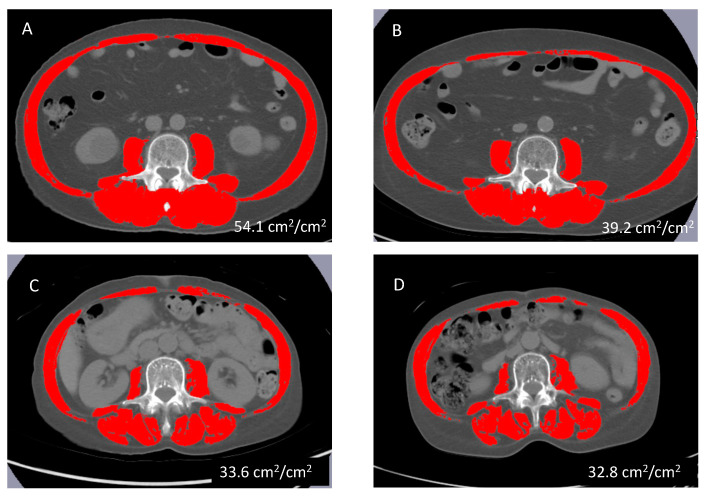

Methods: This retrospective, observational study included 50 MDS patients treated with AZA. Muscle mass was evaluated using the skeletal muscle index (SMI), which is the area of muscle mass at the third lumbar vertebra on CT images divided by the square of the height.